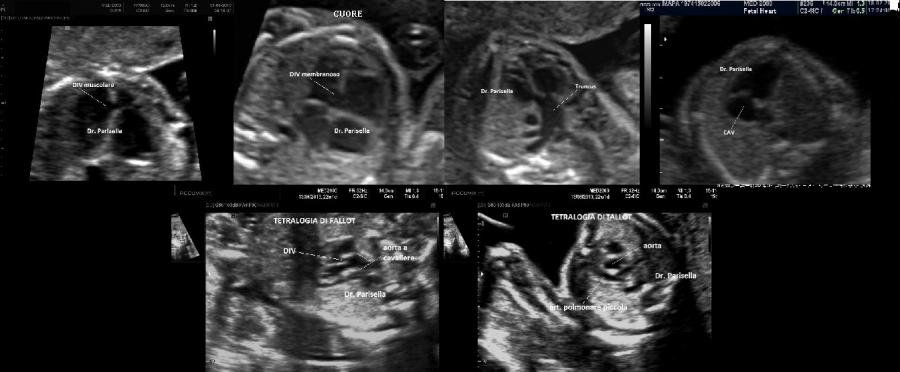

La Sindrome di Gershoni-Baruch รจ una rara malformazione congenita multipla caratterizzata da onfalocele, ernia diaframmatica, anomalie cardiovascolari e difetti radiali.